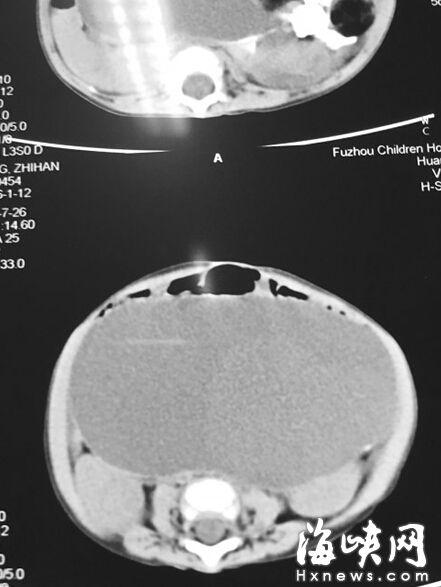

CT顯示,小云腹腔被畸胎瘤霸占

7月22日,家人抱著小云到福州兒童醫(yī)院,福州兒童醫(yī)院副院長(zhǎng)、小兒外科學(xué)博士林芃一摸她肚子,推斷可能是巨結(jié)腸或腫瘤。果然,B超結(jié)果顯示,小云 的左側(cè)腹膜后藏著一個(gè)巨大腫瘤,被腸管擋住了,為此多次漏診。腫瘤直徑約20厘米,幾乎霸占整個(gè)腹腔。7月29日,醫(yī)生花了3個(gè)小時(shí)剝離腫瘤,其皮質(zhì)硬。 醫(yī)生將瘤中的液體吸出500多毫升,“排球”癟了1/3,才被順利取出。這是一個(gè)畸胎瘤,足有2斤重,這么大的很罕見。但畸胎瘤分化不成熟,沒(méi)有成形的毛 發(fā)、牙齒等組織,很可能是惡性腫瘤,目前還在等病理報(bào)告。